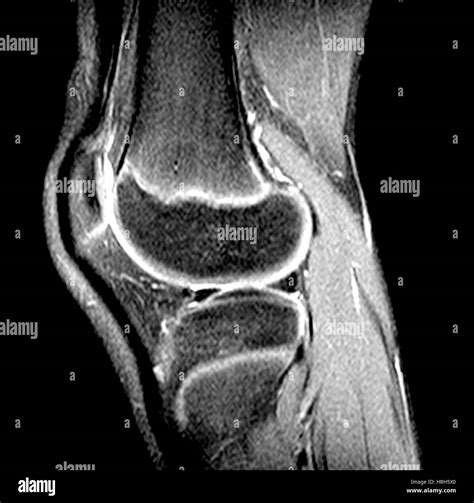

If you have recently experienced persistent joint pain, instability, or a specific injury, your healthcare provider may have recommended a diagnostic scan to get a clearer picture of what is happening inside your joint. Knee MRI images are the gold standard in diagnostic imaging for soft tissue injuries, providing incredibly detailed views that X-rays simply cannot match. Unlike X-rays, which primarily show bone structure, magnetic resonance imaging (MRI) uses powerful magnets and radio waves to create cross-sectional images of the ligaments, tendons, cartilage, and muscles that stabilize your knee. Understanding what these images show and why they are necessary can help demystify the diagnostic process and prepare you for your appointment.

Interpreting knee MRI images is a skill reserved for radiologists, who analyze the scan and produce a detailed report for your referring physician. However, having a basic understanding of what they are looking for can help you better understand your diagnosis. Radiologists look for changes in signal intensity; healthy tissue typically appears in a predictable pattern, while injured or diseased tissue will show up as "brighter" or "darker" areas, known as signal abnormalities.

Bone (Cortical) Appears as a dark outer edge due to low water content.

Ligaments & Tendons Normally appear very dark (low signal) in all imaging sequences.

Meniscus Typically dark; bright signal within the meniscus often indicates a tear.

Joint Fluid Appears dark on T1-weighted images and bright on T2-weighted images.

Bone Marrow Variable signal intensity depending on fat and water content.

When you receive your results, the radiologist’s report will describe these findings in technical terms. For instance, they might describe a high-signal intensity within the meniscus, which suggests a possible tear, or they may note the presence of an effusion, which is an excess accumulation of fluid in the joint, often indicating inflammation or injury.